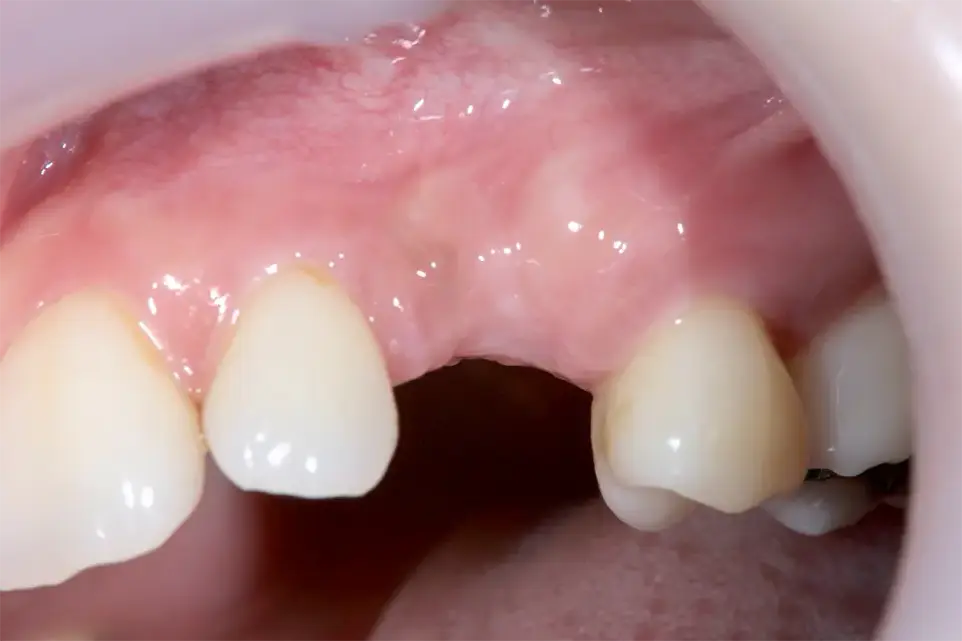

症例5

初診時

レントゲン(骨造成前)

| 患者の症状 | 今まで可撤式部分入れ歯をしていたがインプラント治療希望。他のインプラントクリニックを2件受診したが骨がないので出来ないと言われた。

視診では顕著な骨量不足は認められないがCTで精査したところ垂直的に顕著な骨量不足が認められた。 チタンメッシュによる骨造成およびインプラント治療。 |

| 治療結果 | 術後10年以上経過しているが審美的にも機能的にも非常に満足している。 |